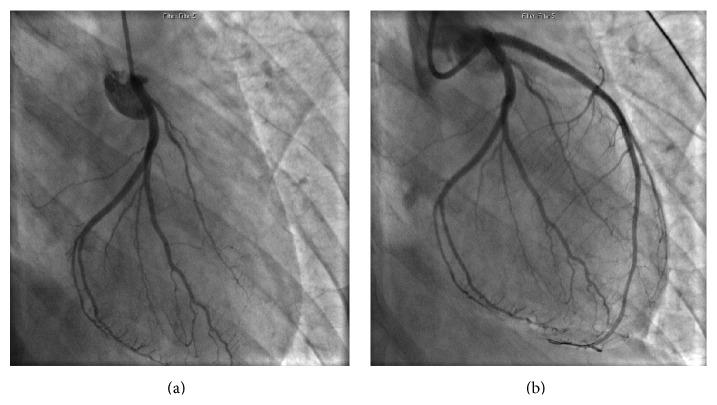

Blunt trauma to the chest resulting in coronary thrombosis and ST elevation myocardial infarction (STEMI) is a rare but well-described occurrence in adults. Angiography in such cases has generally disclosed complete epicardial coronary occlusion with thrombus, indistinguishable from the findings commonly found in spontaneous plaque rupture due to atherosclerotic disease. In all previously reported cases in which coronary interrogation with intravascular ultrasound (IVUS) was performed in association with acute revascularization, coronary artery dissection was implicated as the etiology of coronary thrombosis. We present the first case report of blunt trauma-associated coronary thrombosis without underlying atherosclerosis or coronary dissection, as documented by IVUS imaging.

钝性胸部创伤导致冠状动脉血栓形成和ST段抬高型心肌梗死(STEMI)在成人中虽罕见但已有详尽描述。此类病例的血管造影通常显示冠状动脉完全闭塞并伴有血栓,与动脉粥样硬化疾病所致自发性斑块破裂的常见表现难以区分。在先前所有报道的病例中,在急性血运重建时同时进行血管内超声(IVUS)检查,均提示冠状动脉夹层是冠状动脉血栓形成的病因。我们报告首例经IVUS成像证实的钝性创伤相关性冠状动脉血栓形成病例,该病例无潜在动脉粥样硬化或冠状动脉夹层。